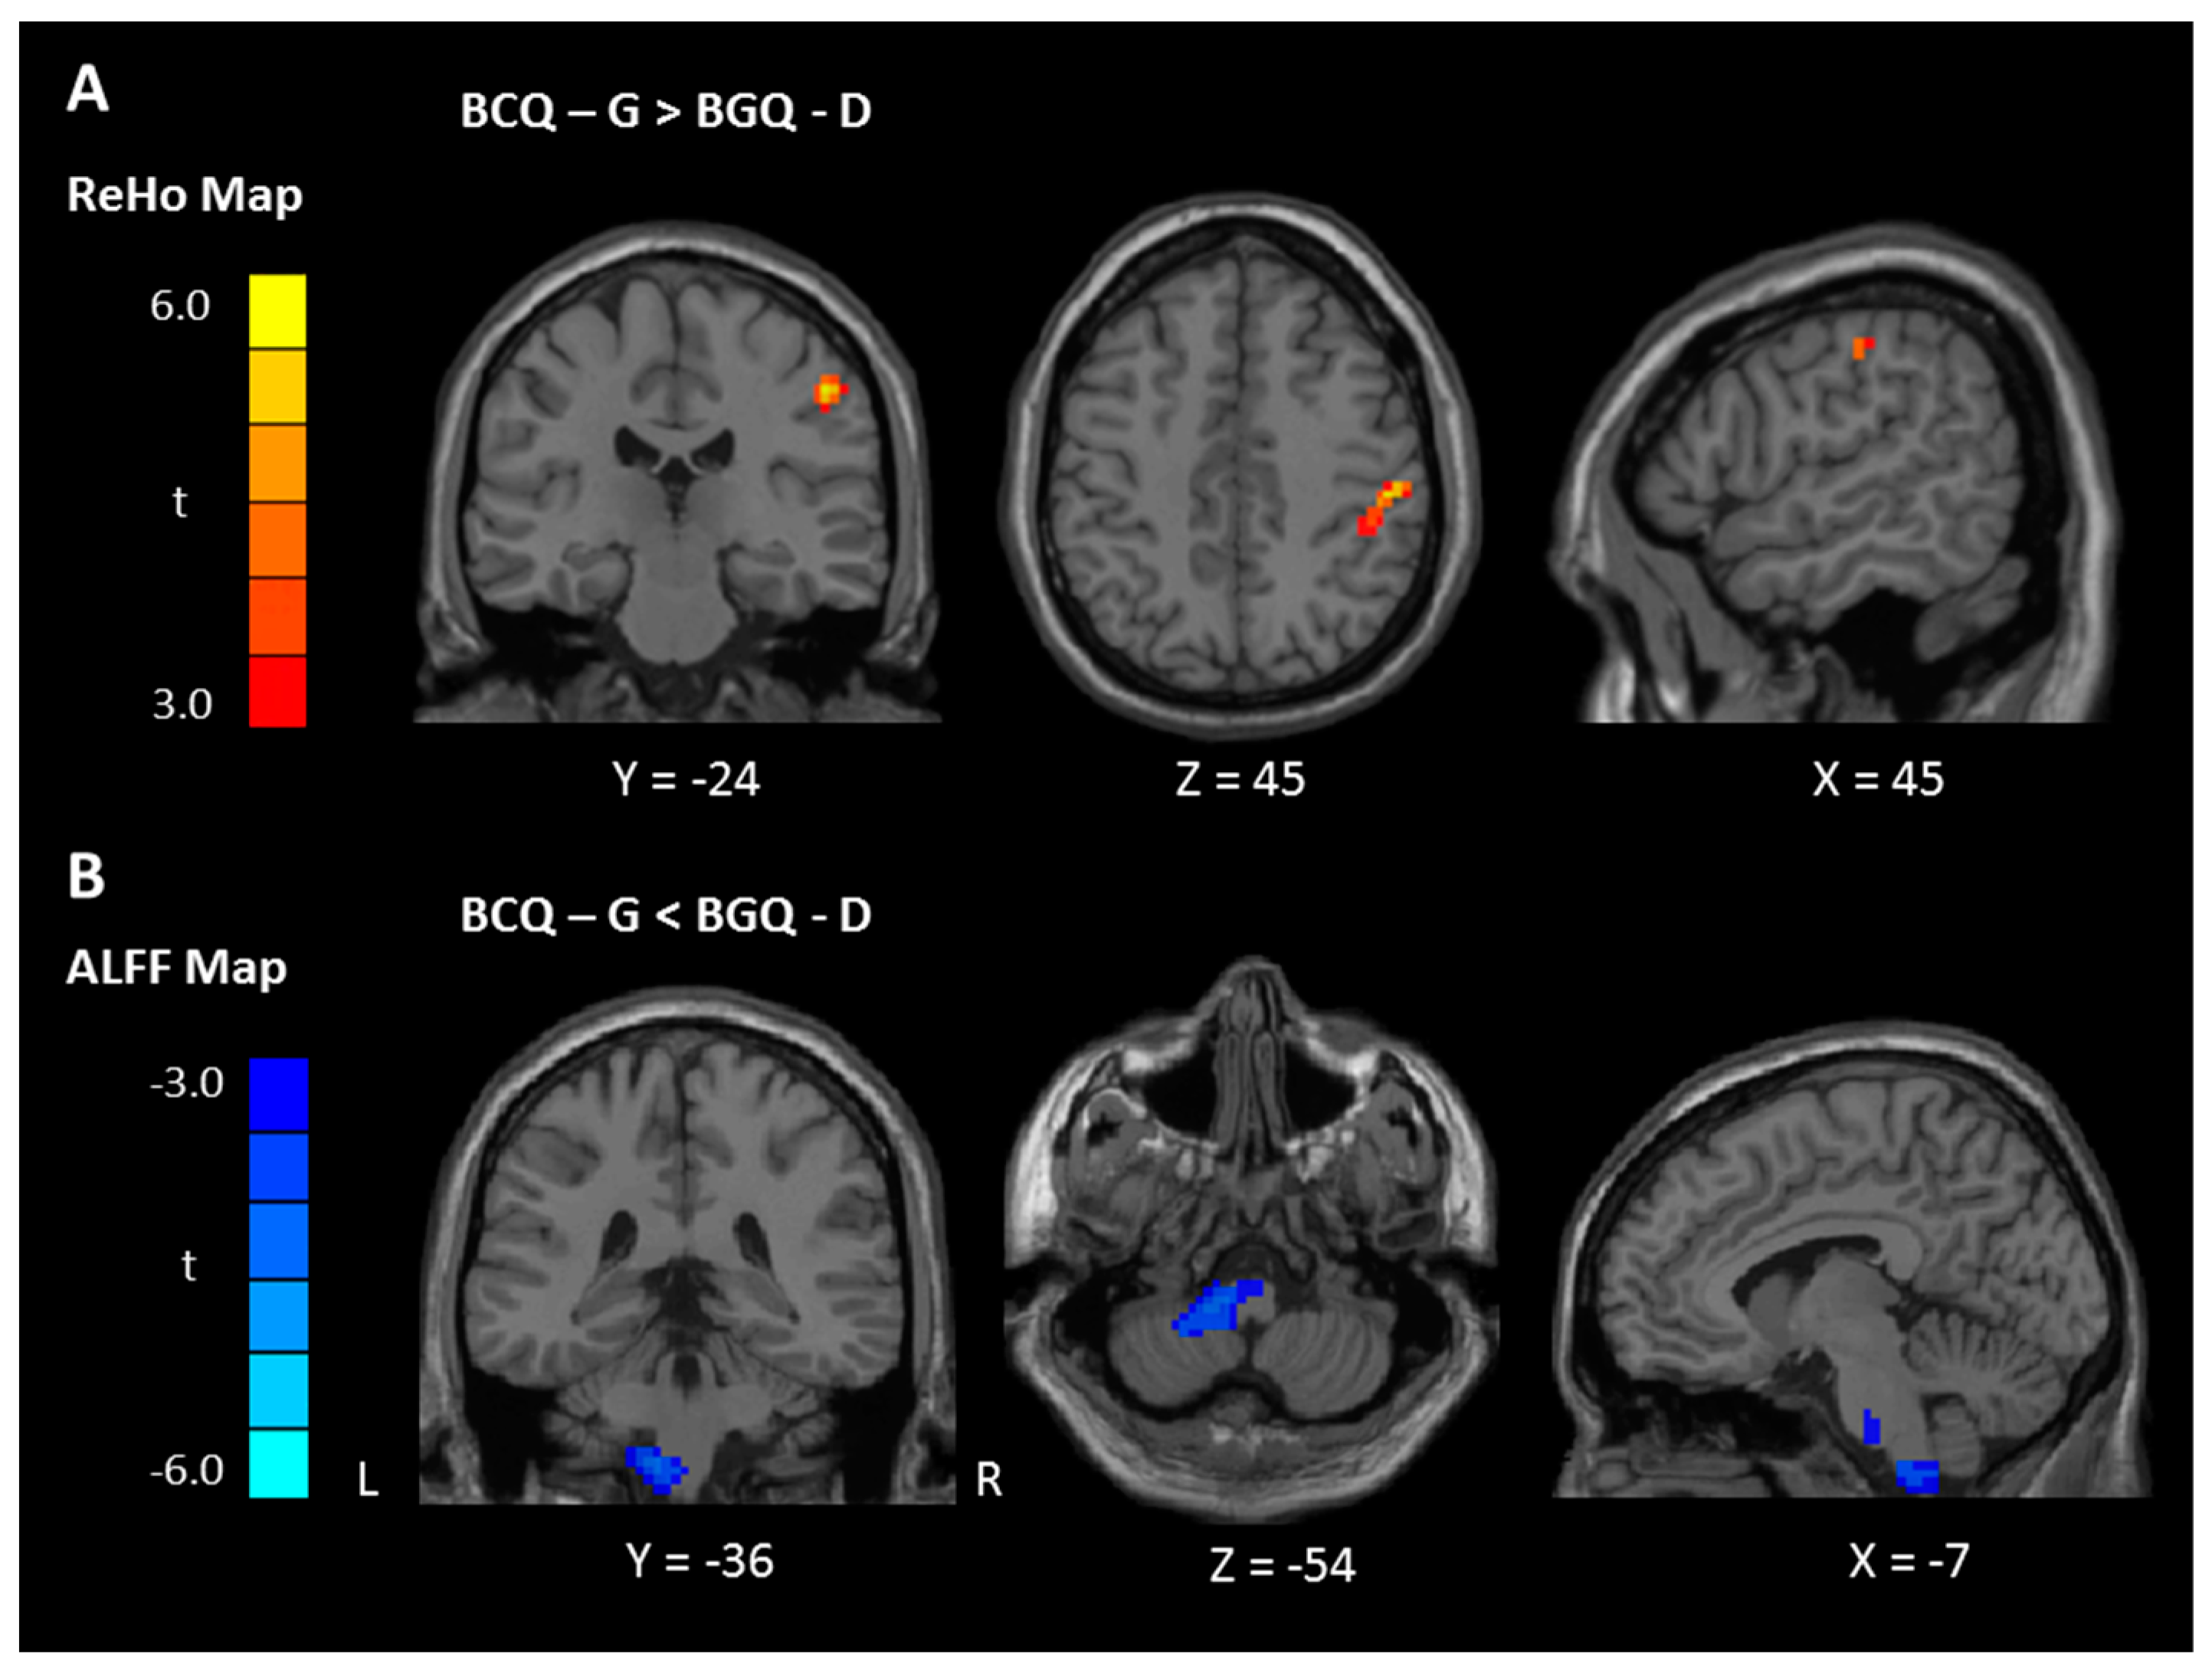

3.3. ReHo and ALFF Analyses

| Contrast | Region | BA | Size | t Score | Peak Coordinate | ||

|---|---|---|---|---|---|---|---|

| x | y | z | |||||

| ReHo | |||||||

| Between-group * | |||||||

| Gentleness > Deficiency | Postcentral gyrus | 2 | 69 | 5.37 | 51 | −24 | 45 |

| Gentleness < Deficiency | NS | ||||||

| ALFF | |||||||

| Between-group * | |||||||

| Gentleness > Deficiency | NS | ||||||

| Gentleness < Deficiency | Pons/Cerebellum, Left | 85 | −3.86 | −12 | −36 | −54 | |